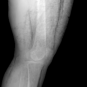

In this section, we provide qualitative and quantitative results of the two proposed diffusion-based methods and compare them with the baseline U-Net model. The first column of Fig. 3 showcases six randomly selected conditions: (a0)-(c0) show contour segmentations, and (d0)-(f0) denote segmentations containing contour and bones. In Fig. 3 (a1)-(f1), the images generated by U-Net contain blurred fine details in locations where bones overlap, despite maintaining the given shape, as highlighted by the red circle. In contrast, the results from CSM appear more realistic than the U-Net. However, their quality decreases with introduced constraints, as indicated by the red arrow in Fig. 3 (d2) and (f2). The results from CTM not only achieve nearly the same level of fineness as the labels but also provide reasonable results with respect to the given conditions as illustrated in the fourth column.

Table I summarizes the quantitative results averaged across all testing data. The evaluation metrics include mean absolute error (MAE) and peak signal-to-noise ratio (PSNR). We observed that CTM performs substantially better than U-Net and CSM under both segmentation-based conditions, and CSM performs worse than the U-Net.

Unlike the U-Net which learns a mapping function between input and output, the diffusion models can implicitly capture the underlying data distribution from the training data and then sample it, preventing the loss of fine details on the pixel level. However, in CSM, conditions are incorporated only at the first sampling step while being perturbed, which results in imprecise conditional information. Instead, CTM provides an estimated score function of the conditional distribution for each sampling step, accommodating both reliability and realism. Nonetheless, presently generated X-ray images only encompass independent 2D conditional information, which may introduce geometric inconsistencies between a set of projections. Future research will focus on modeling 3D probabilistic distributions with the provided 2D conditions to enable CT reconstruction from the generated projections. In addition, clinical datasets will also be incorporated.